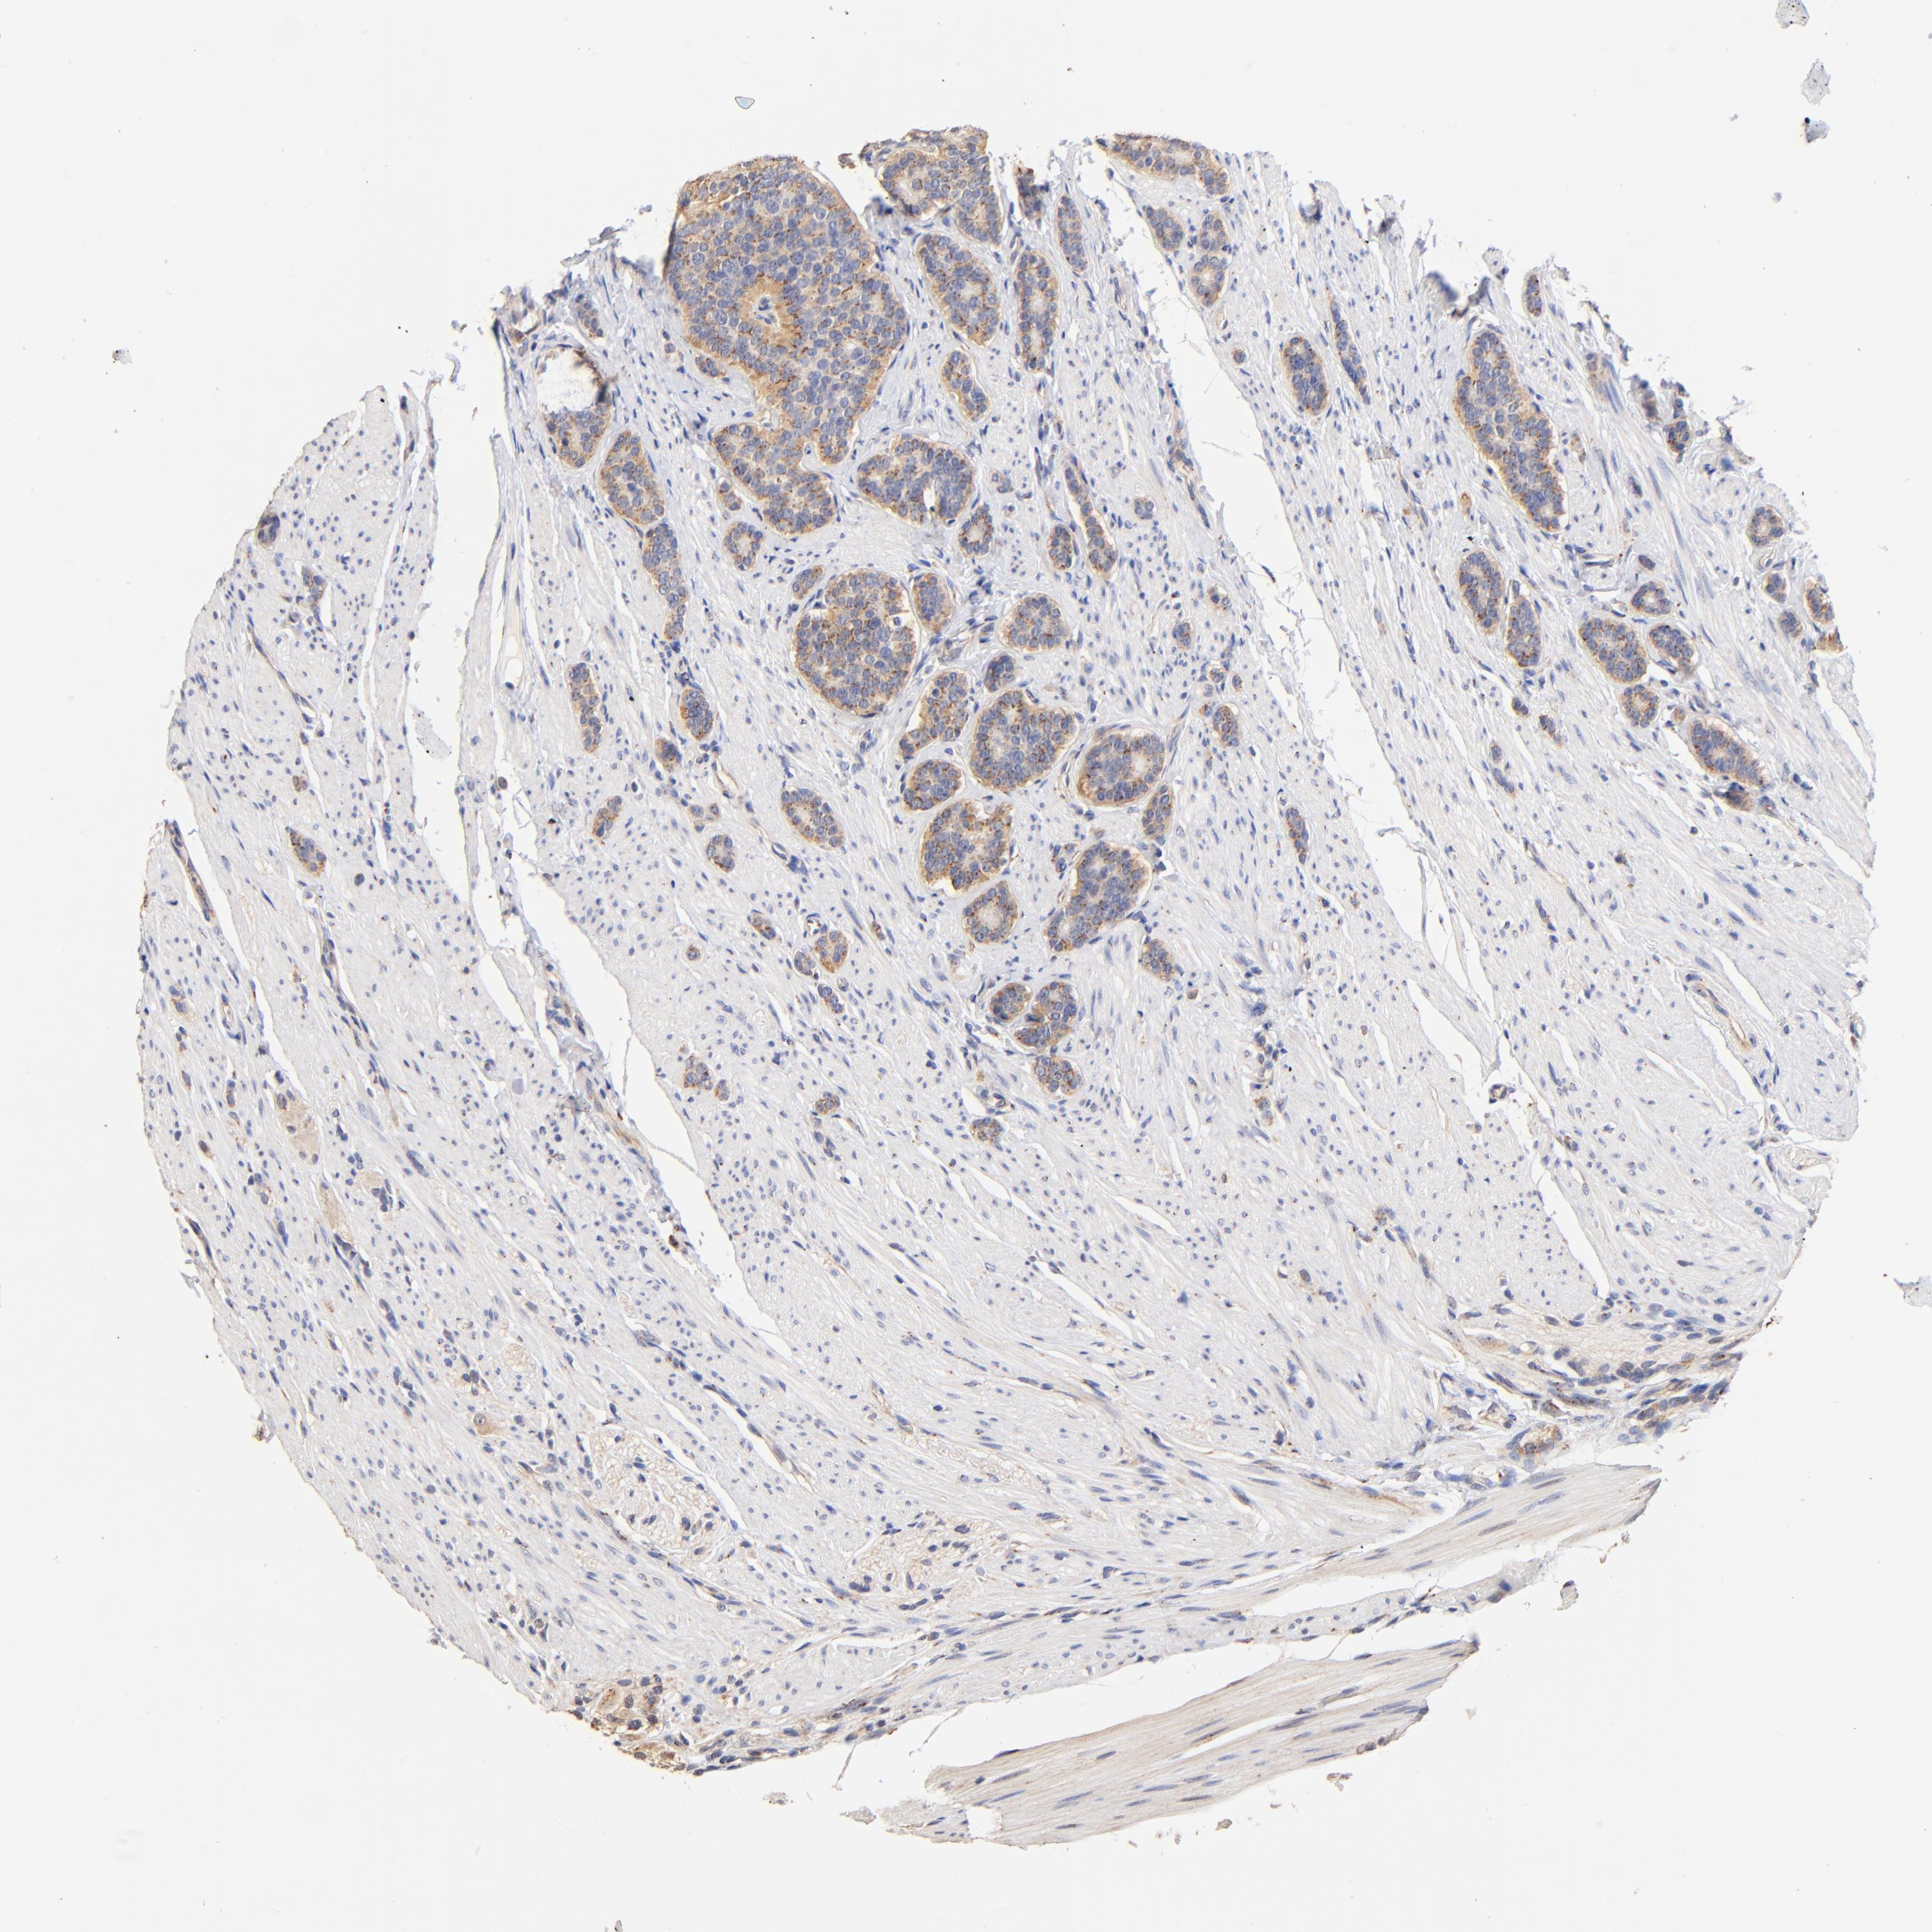

CARCINOID - Protein expressioni

A mouse-over function shows sample information and annotation data. Click on an image to view it in a full screen mode. Samples can be filtered based on level of antibody staining by selecting one or several of the following categories: high, medium, low and not detected. The assay and annotation is described here.

Antibody stainingi

Antibody staining in the annotated cell types in the current human tissue is reported as not detected, low, medium, or high, based on conventional immunohistochemistry profiling in selected tissues. This score is based on the combination of the staining intensity and fraction of stained cells.

Each image is clickable and will lead to virtual microscopy that enables deeper exploration of all samples and also displays staining intensity scores, fraction scores and subcellular localization as well as patient and tissue information for each sample.

Antibody HPA002552

Carcinoid, malignant, NOS